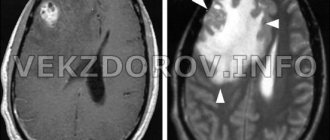

Понятие о патологии Острый рассеянный энцефаломиелит является достаточно опасным недугом, при котором поражаются головной

В центральной нервной системе существуют различные варианты опухолей. Источником их являются различные ткани. Известно,

Аневризматические САК/разрыв аневризмы Примерно 85% нетравматических САК развиваются на фоне аневризмы. Частота аневризм-.postmortem 2-5%,